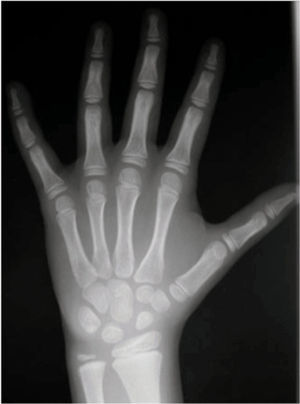

En cuanto a consideraciones técnicas, la dosis de radiación efectiva recibida por la realización de una radiografía posteroanterior de mano-muñeca (fig. 1) para la valoración de la EO es menos de 0,00012 mSv, equivalente a menos de 20min de radiación basal natural o 2 min de un vuelo transatlántico. Así, en el ámbito de la clínica, el riesgo es mínimo, aunque como cualquier otra prueba complementaria no ha de realizarse sin una justificación1,4.

Radiografía de la mano izquierda mostrando los contornos detectados por el método BoneXpert: radio y cúbito distal, metacarpos y falanges. Cada uno de los 15 huesos tiene una edad ósea (EO) asignada y la media resultante es la EO obtenida.